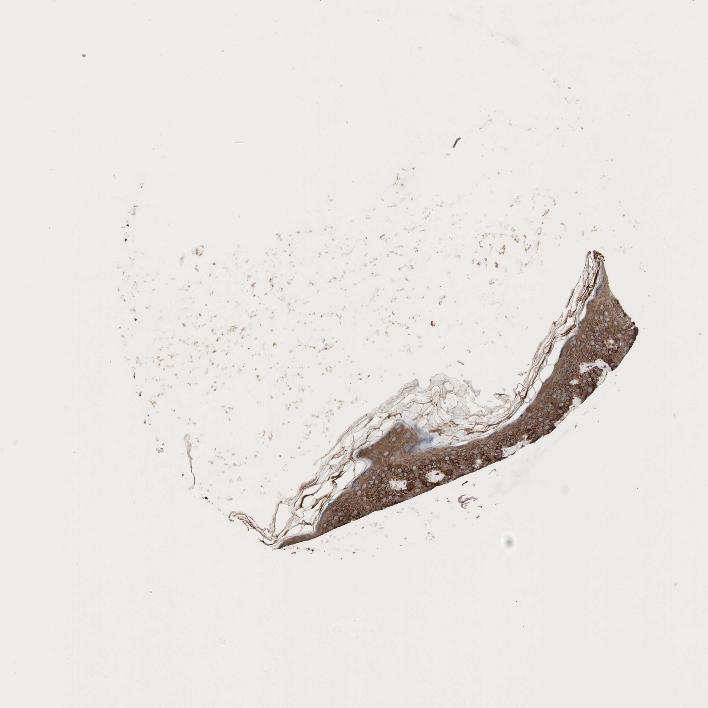

SKIN 1 - Antibody stainingi

Antibody staining in the annotated cell types in the current human tissue is reported as not detected, low, medium, or high, based on conventional immunohistochemistry profiling in selected tissues. This score is based on the combination of the staining intensity and fraction of stained cells.

Each image is clickable and will lead to virtual microscopy that enables deeper exploration of all samples and also displays staining intensity scores, fraction scores and subcellular localization as well as patient and tissue information for each sample.

Antibody HPA056141Antibody CAB005331

Langerhans Not detectedLow

Fibroblasts MediumHigh

Keratinocytes Not detectedHigh

Melanocytes LowHigh